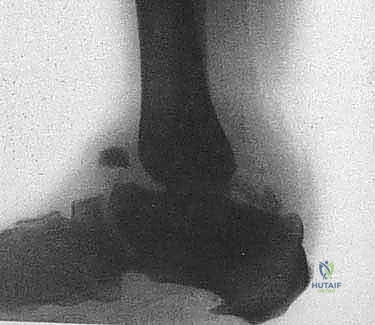

Resulting severe ankle and hindfoot deformities frequently are non-braceable. Bearing weight on such deformities can result in abnormal ipsilateral stresses on the knee, leg, ankle, hindfoot, and forefoot, causing ligament laxity, stress fractures, and recurrent ulcerations leading to cellulitis, abscess, and osteomyelitis ( FIG 1 ).

FIG 1 • A. Unbraceable Charcot ankle and hindfoot deformity, even with a Charcot retention orthotic walker (CROW). B. Lateral radiograph of Charcot neuroarthropathy of the ankle.